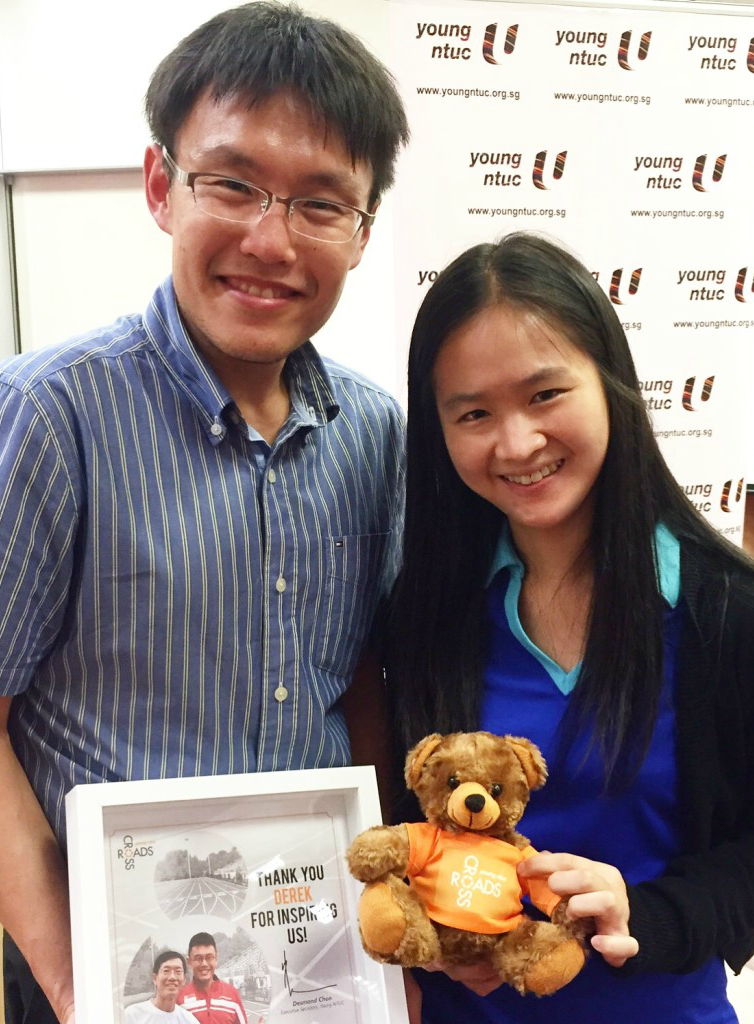

So what is Zika and what should you know about it? Said Dr Derek Li, 34, a General Practitioner who is commonly known as one of Singapore’s ‘Running Doctors’, “Zika is characterised by fever and rash, plus joint aches or conjunctivitis (red eyes). If you have other symptoms together with the fever – such as flu or stomachache, then it’s unlikely to be Zika.”

The Zika virus however, is not as serious a threat as dengue generally is, added the doctor.

He said “But then again, a lot of people may be infected with Zika and not exhibit the telltale signs. And the average time for recovery is about three to five days.”

Continued Dr Li, “Zika also tends not to be life threatening so by comparison, dengue is a lot more dangerous. The main danger of Zika remains the threat to pregnant women in the form of microcephaly as far as we know for now.”

Added Dr Li, “But then again, there is a lot that we still do not know about Zika and even the scientific research is very conflicting. We do know that Zika can cause microcephaly in unborn babies and may even cause stillbirth but the how and why are still unknown.”

So the current recommendation then, is for infected women to wait some time – before they try for a baby.

Explained the doctor, “Infected women should avoid pregnancy within EIGHT WEEKS of Zika infection, but that is the extent of what we are fairly certain of at this time. Recently there were some studies showing a possible link between Zika infection and dementia, but that remains to be fully corroborated by others.”

Many may know that the Zika virus spreads primarily through the bite of the Aedes mosquito, but Dr Li pointed out that it can also be found in the breastmilk of infected mothers too.

The doctor added “But it is not clear if that poses any threat to a breastfeeding baby. The Zika virus can also be found in the sperm and ova of infected adults so foetuses can be affected this way.”

For runners in particular, Dr Li feels that that no special precautions really need to be taken.

He added, “We should bear in mind that Zika and Dengue spread in the same way, so there is really no need to change what you are doing unless you are planning for a baby. Running in general though, does increase your risk of mosquito bites, only if you run in areas that are prone to mosquito infestation, I suppose. That would include places like the Macritchie and Bukit Timah trails, though they are not currently recognised as Zika or Dengue hotspots.”

The reason is because according to Dr Li, there is typically less ventilation in the trails.

He explained “So in theory the chances of getting bitten are higher due to the stillness of the air. I would recommend choosing areas with the potential for more wind to run in, such as coastal park roads and avoid trails altogether if possible. Or ensure adequate clothing plus the usage of mosquito repellants if running in the trails.”

Dr Li also added that mosquitoes tend to be most active at nights. Said the doctor, “This is something to bear in mind when you are running. They are also attracted to body heat and the carbon dioxide signature from our breathing. It may be helpful to have more body coverage through clothing like arm sleeves and use insect repellant around the neck, forearms and legs.”

REPELLING MOSQUITOES

In choosing mosquito repellents, Dr Li does not recommend a specific brand though. He said “I don’t know of any one brand that is better than the others. The ones you can find off the shelf in pharmacies are all deemed safe and effective, even for pregnant women.”

And due to the “kiasu” nature of many Singaporeans though, most pharmacies are unfortunately low on stock, or sold out of mosquito repellent products now. Said Dr Li, “If that’s the case, I’m told that lemon grass works, but I have no idea if that is actually true.”

Added the doctor, “But then again, first and foremost, we should be mindful of leaving stagnant water around that serve as breeding ground for mosquitoes. Overall these are things that we should all have been doing for years, and the Zika outbreak is a reminder of how important those little preventive measures are.”